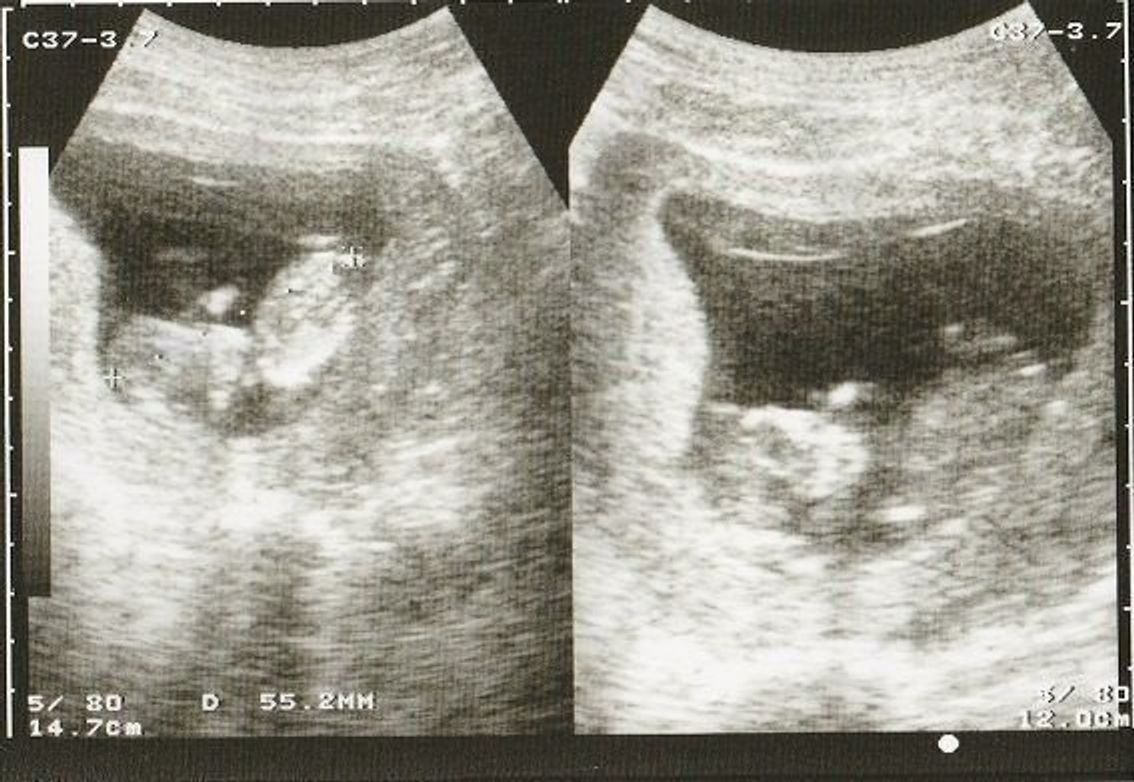

(図C124) 三次元超音波法による胎児像.a:11週胎児,b:12週胎児,c:13週胎児. る.そのため,妊娠12週頃からはBPDを計測して修正する. (4)三次元超音波法による正常胎児像 妊娠5週頃から三次元超音波法による胎芽表面表示が可能である.その全体 胎児の様子 母体の変化 妊娠12週・13週・14週・15週 頭殿長:約4~16cm 体重:約8~1g 身体が完成する 重要な器官の形成が終わります。 歯が作られる 乳歯、永久歯の準備が始まります。 指を吸う 身体の動きが活発に。■胎児と子宮の大きさ 頭殿長(座高)が11cm~12cm 体重は100gほど 子宮底長が14cm~18cmほど

妊娠12~15週目の胎児の大きさ 胎児は16cmの大きさ、体重は15~100gと急激に成長していきます。 BPDは16~33mm程度になります。 体の大きさ以外にも胎児の消化器官が動き、爪や指紋なども形成されていきます。 妊娠16~19週目の胎児の大きさ 身長は16~cm 胎嚢・胎芽の大きさ平均まとめ 今回調査した60名の妊婦の内訳は、自然妊娠が52名、人工受精が2名、体外受精が6名でした。 このうち出産できたのが52名、流産が8名でした。 出産できた52名のうち、6w3dで心拍確認済みとなったのは86%にあたる45名でした私は12週に入った頃です。 最初に産婦人科で診てもらったのが8週目のときでした! 私も「小さすぎる、ちゃんと育たないかも」と言われ、10日後に また来てくださいといわれました。 小さくなくても、11週くらいまでは10%くらい流産の心配があるそうです。

これは先ほど説明した 胎児の推定体重を、「胎児発育曲線」グラフに当てはめて判断しています。 胎児発育曲線グラフとは、正期産(37週~41週のお産)で生まれた 正常な体重の赤ちゃんの胎児時代の推定体重データを元に、 妊娠週数ごとの基準値、つまり平均値をグラフ化したものです。妊娠12週5日(12w5d)の超音波(エコー)写真 順調に育ち大きさも735㎜でした! 先生にファイティングポーズしてますね。と言われ笑ってしまいました(笑) 何と戦っていたのかしら。 次の検診が楽しみです! たばこが母体や胎児に及ぼす影響は? 中でも赤ちゃんの大きさは、発育状態を知るための大事な情報。 BPD(赤ちゃんの頭の左右の幅)、ACまたはFTA(おなか回り、またはおなかの横断面積)、FL(赤ちゃんの太ももの骨の長さ)といった、各部位を測って 推定体重 を出し、週数に応じた平均値と比べて、大きくはずれていないか確認します。 また、大きさを調べることで、赤ちゃんや母体のトラブルを